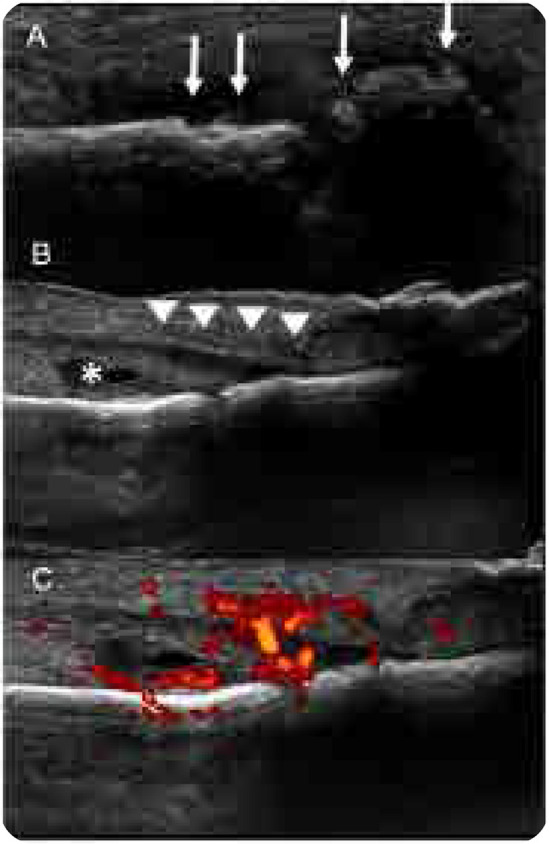

Psoriatic Onycho-Pachydermo Periostitis (POPP).